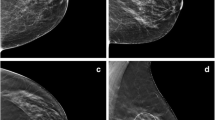

Figure 4 shows an example of the effects of increasing quantum noise in the image corresponding to a case with calcifications.